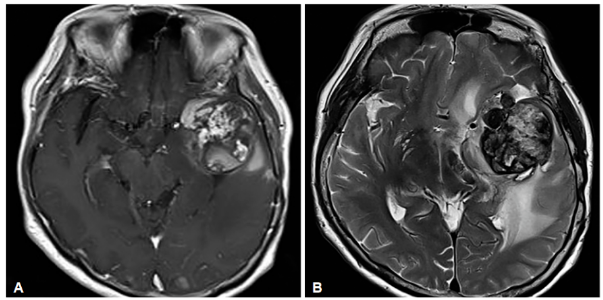

一位72岁的脑膜瘤患者就经历了这样的艰难历程。她在手术后又接受了放疗,本以为能控制住病情,却没想到多年后,一个4.3厘米的肿块伴随着严重脑水肿突然出现。经过详细检查,医生们得出了一个令人唏嘘的结论:这不是肿瘤复发,而是放疗引发的海绵状血管瘤。

这种被称为RICH(放疗诱发海绵状血管瘤)的病变,本质上是放疗对脑血管造成的晚期损伤。更让人心痛的是,研究表明:患者接受放疗时越年轻,发生这种并发症的风险就越高。

图1:放射诱发海绵状血管瘤(RICH)的影像学表现。